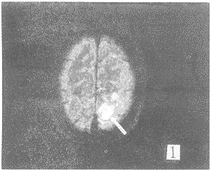

在FLAIR序列所发现81个病灶中,FSET2序列能显示的有66个,FSET2序列对病变显示率 为81.4%。FSET2序列未显示的15个病灶均位于侧脑室下、脑室旁及脑灰质区(图1,2) 。位 于脑室下的病灶,T2像未能显示。而位于基底节区,脑白质区的病灶,FLAIR及FSET2序列都 能显示。T2加权像上,所有病灶均为高信号。但在FLAIR序列,有2个病灶为低信号,1例出 血,出血灶的低信号部份T2像未能显示。另1例是T2加权像没能显示的血管畸形远端侧枝 循环(图3,4),此例为左侧颈内动脉畸形,左顶叶侧枝循环,T2像未能显示。在T2像上没能 显示而FLAIR像显示的15个病灶中,有10例为脑梗塞、脱髓鞘病变和皮层下动脉硬化性脑病 , 病灶位于脑灰质,受脑脊液影响T2像未能显示。2例为转移瘤(图5,6),肿瘤位于脑灰质,T 2像仅见水肿影。2例为脑炎、脑膜炎(图7,8),在T2像上病灶完全被脑沟中的脑脊液所掩盖 。

图1 FLAIR像示左顶叶脑梗塞灶,而FSET2像(图2)仅可见水肿影